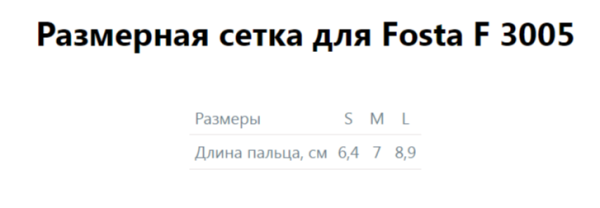

Тип

Бандажи для пальцев кисти

Количество в упаковке

—

1

Пол

—

Для женщин, Для мужчин

Область применения

—

Рука

Артикул

—

656860

- фиксация и стабилизация пальцев кисти.

- переломы межфаланговых суставов

- переломы фаланг пальцев

- повреждение сгибателей пальцев кисти

- период реабилитации после операций пальцев кисти